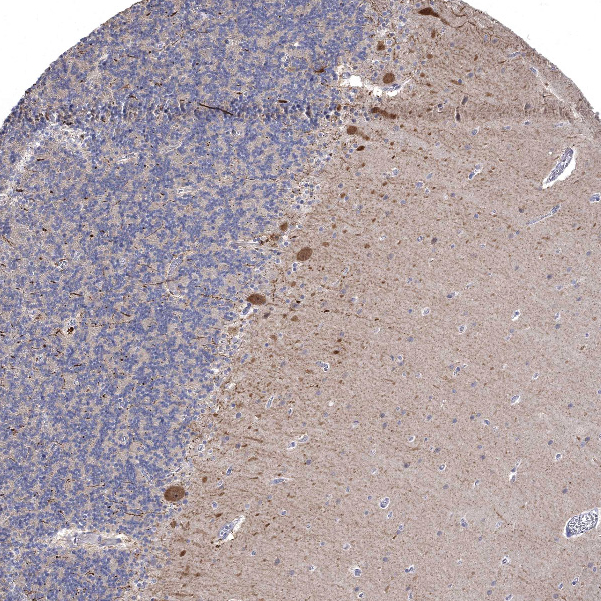

Immunohistochemical staining of human Cerebral cortex shows moderate cytoplasmic positivity in neuronal cells.